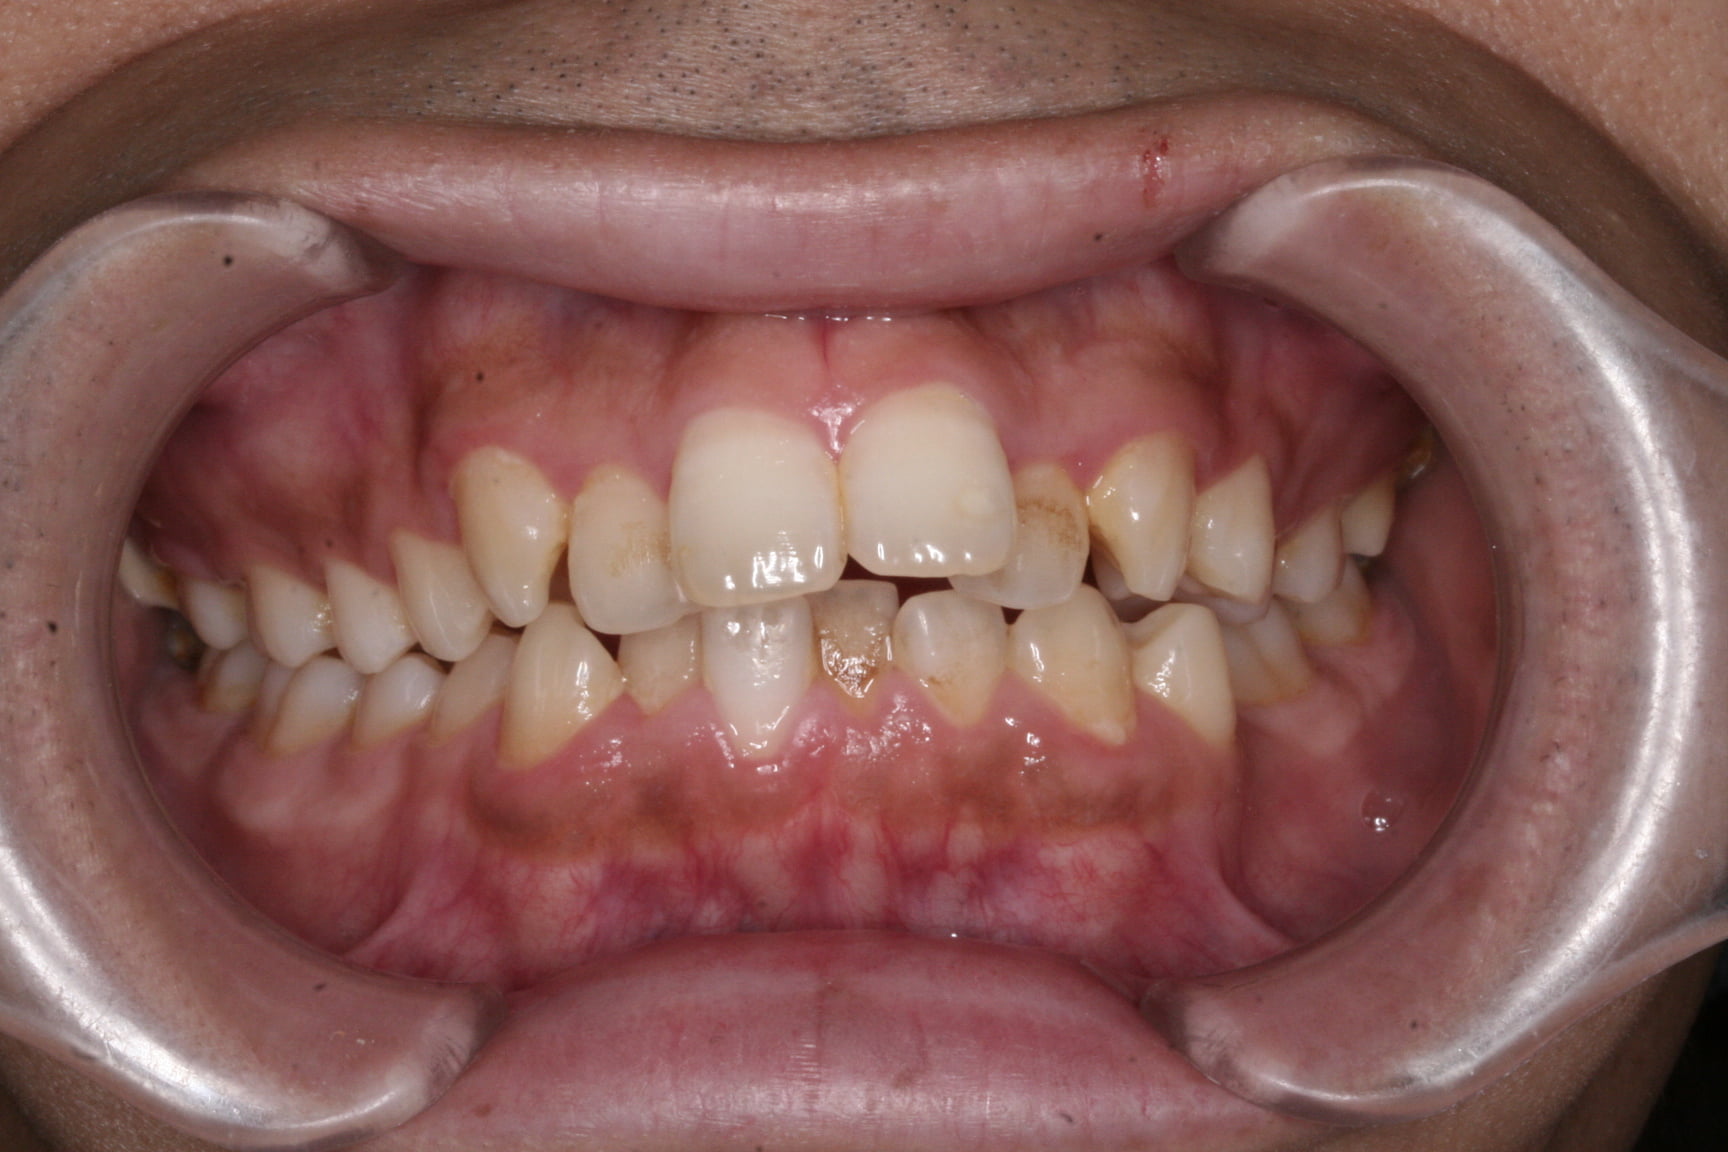

出っ歯を治したい

年齢層 30代

性別 女性

主訴 【主訴】出っ歯を治したい 【診断・症状】上下凸凹、出っ歯(上顎前突)

治療費用 検査・診断:38,500-/裏側矯正治療:1,397,000-(※全て税込)

治療期間 約2年半(33回)

抜歯 有(上4,4、下5,5)

矯正の装置 裏側矯正(舌側矯正)

副作用、リスク 歯肉退縮,歯根吸収,疼痛,咬合の違和感,装置の違和感,虫歯,歯肉炎

case20_出っ歯_before

Before

case20_出っ歯_after

After